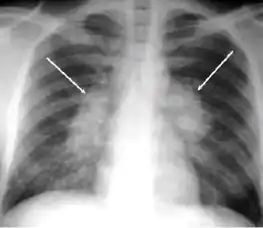

Chest X-ray of a person with advanced tuberculosis: Infection in both lungs is marked by white arrow-heads, and the formation of a cavity is marked by black arrows.

5. Hilar or mediastinal lymphadenopathy (bihilar lymphadenopathy) - Enlargement of lymph nodes in one or both hila or within the mediastinum, with or without associated atelectasis or consolidation.

-

Chest x-ray showing bilateral hilar adenopathy of primary pulmonary TB